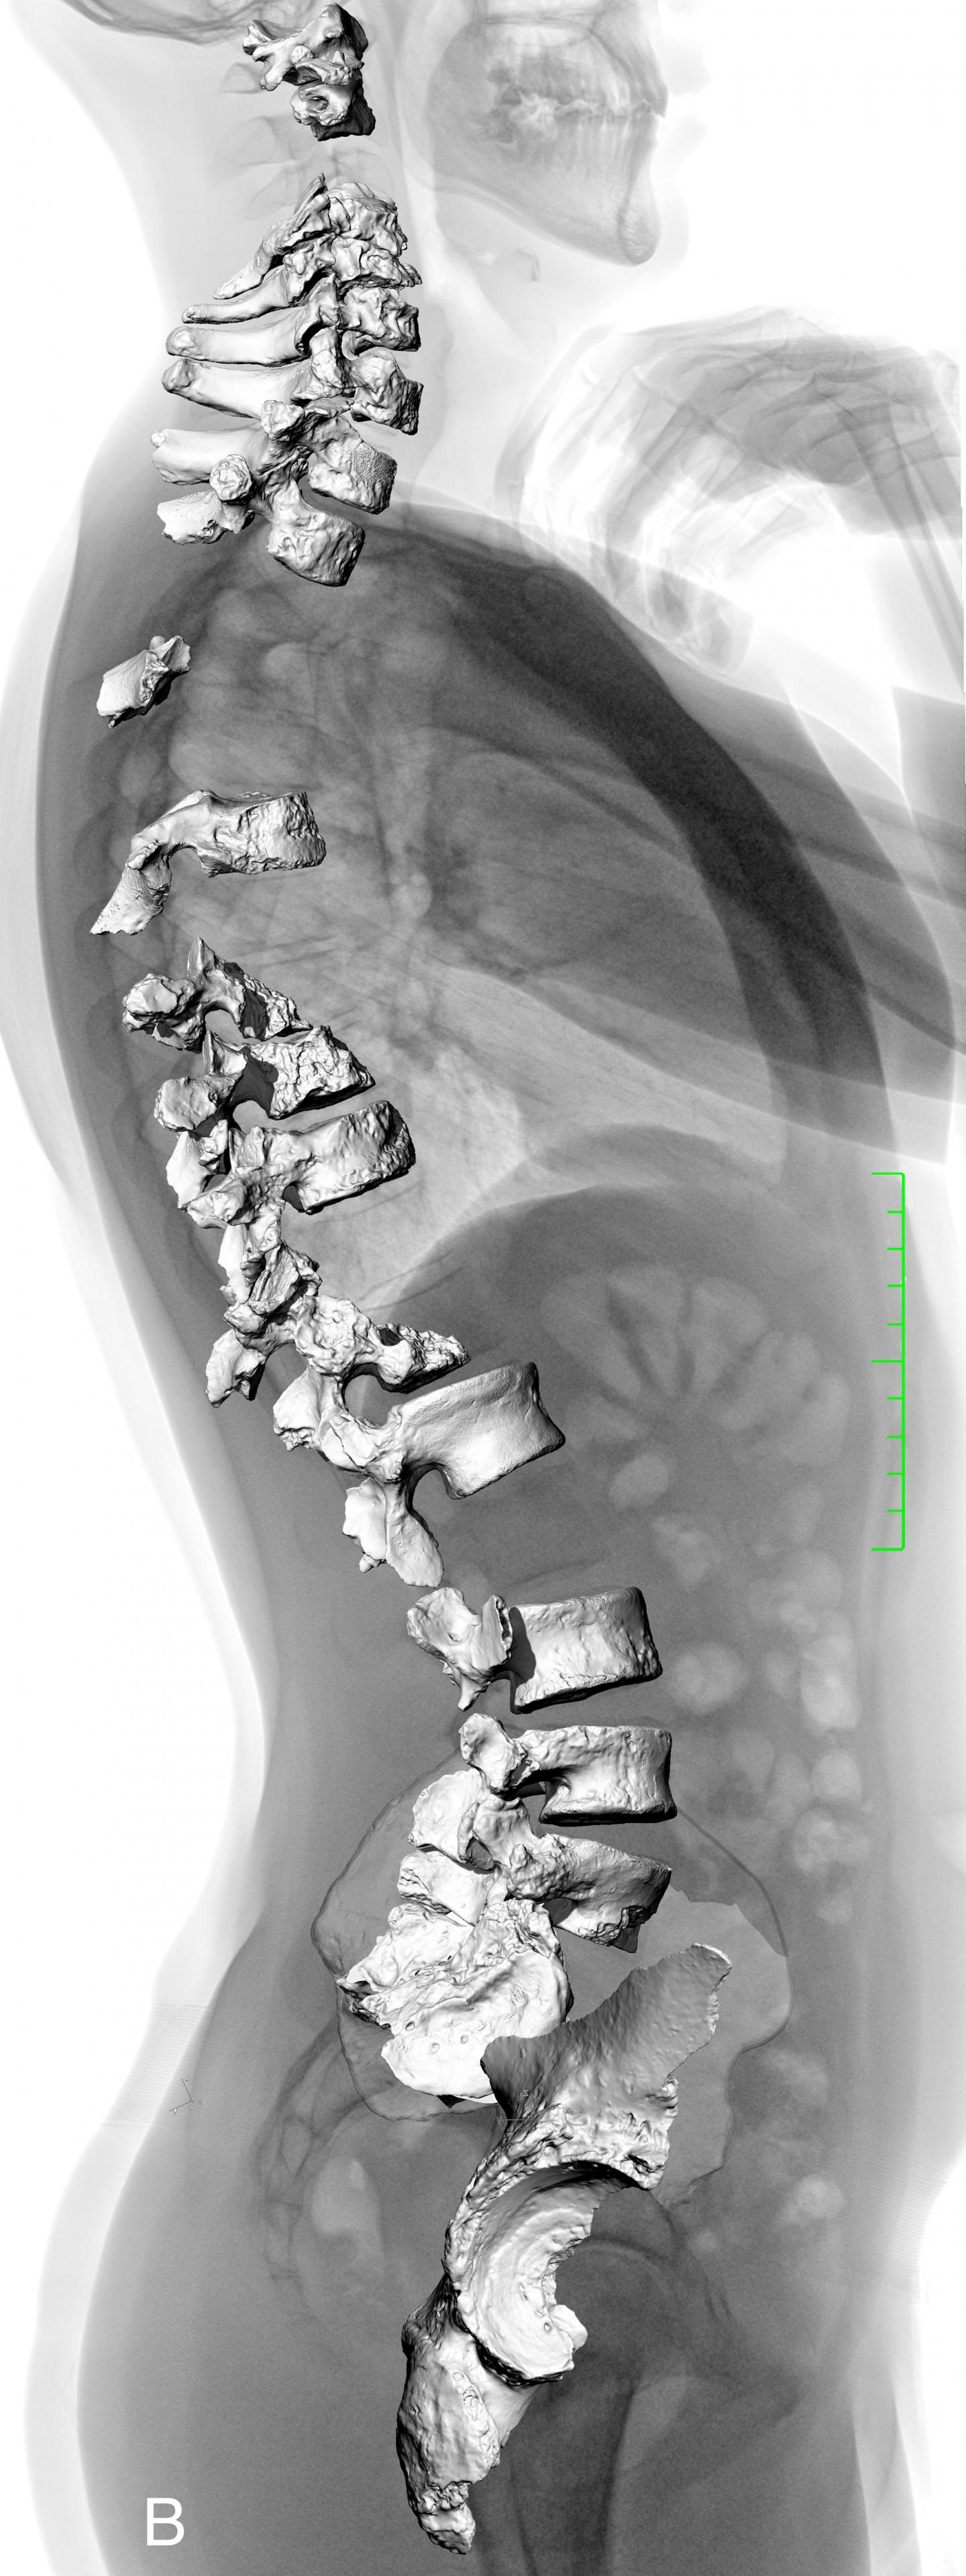

The La Chapelle-aux-Saints Vertebrae, Superimposed on a Full Body Radiograph of a Modern Human (IMAGE)